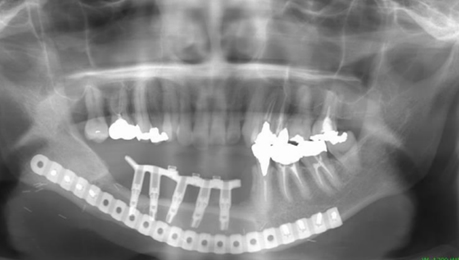

下顎骨を区域切除し、血管吻合を用いた腓骨皮弁で再建を行い、歯科インプラントを腓骨に埋入し、補綴治療を行っている。

移植した腓骨へのインプラント埋入、カスタムメイドアバットメントの作成、装着、義歯装着の流れ。